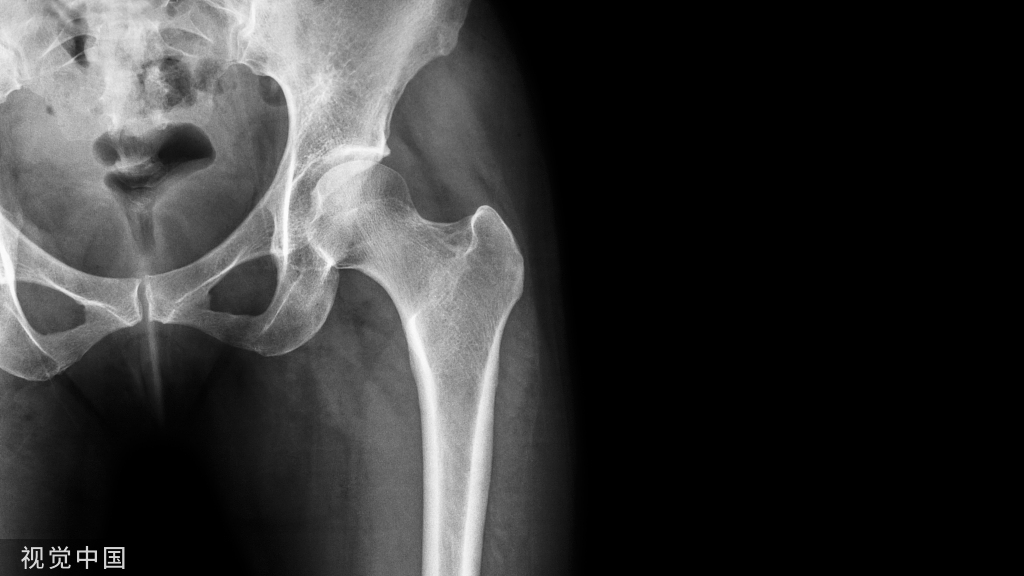

三枚空心拉力螺钉平行固定是股骨颈骨折最常见的内固定方法,但对于Pauwels Ⅲ型、股骨颈后内侧粉碎及严重骨质疏松的股骨颈骨折患者,传统三枚空心拉力螺钉平行固定容易失败。

三枚空心拉力螺钉平行固定是股骨颈骨折最常见的内固定方法,但对于Pauwels Ⅲ型、股骨颈后内侧粉碎及严重骨质疏松的股骨颈骨折患者,传统三枚空心拉力螺钉平行固定容易失败。如Pauwel's Ⅲ型股骨颈内固定术后的总体翻修率高达18%[Slobogean 2015]。

Pauwels Ⅲ型

垂直剪力大,易内翻、固定失败、骨不连

内翻、断钉

股骨颈粉碎骨折(尤其股骨颈后内侧粉碎者)

严重骨质疏松